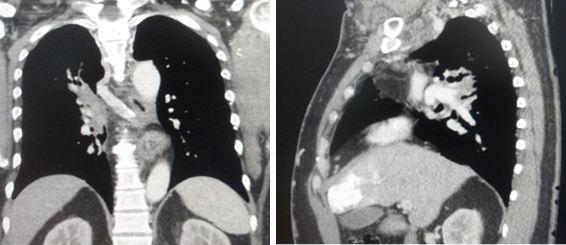

- CT scan showed that there are many lumps all clustered together to cause that swelling.

Medical report of 27 February 2018: Multiple enlarged right level II, bilateral level III and level V and right supraclavicular, right axillary, mediatinum and paraaortic lymphadenopathy. Consistent with recurrence of lymphoma.